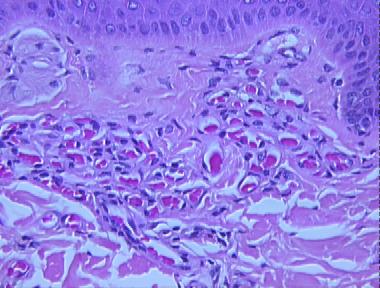

angioma serpiginosum

Histologic Features